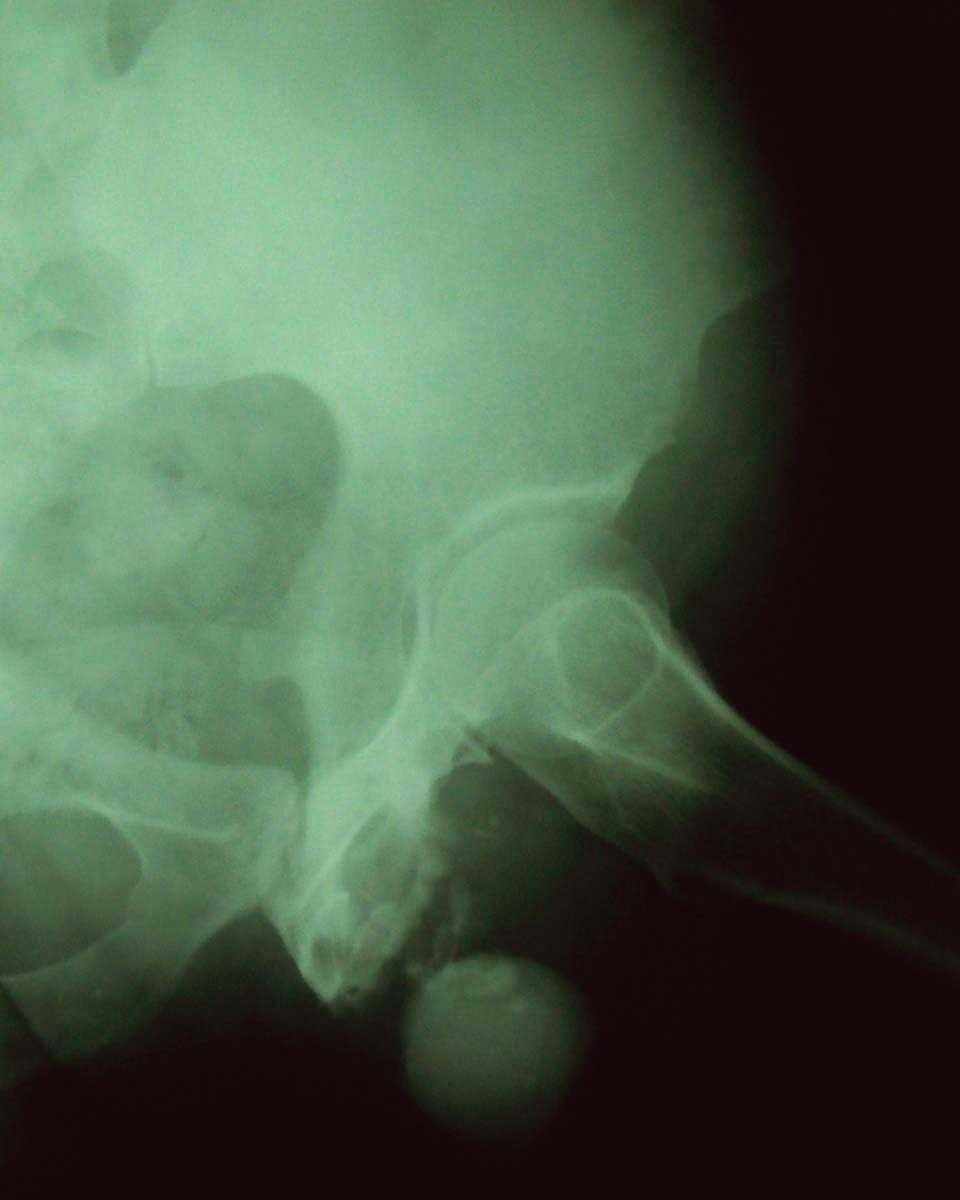

La afectación ósea se detectó con radiografías, tomografía axial computarizada (TAC) y gammagrafía. Los huesos afectos fueron en dos casos las costillas y en uno la mandíbula inferior derecha, la escápula izquierda, el esternón y la rama isquio-pubiana izquierda (fig. 3). La radiografía de tórax demostró tuberculosis pulmonar en tres de los pacientes (50 %): uno con datos radiológicos de diseminación broncógena y dos compatibles con tuberculosis antigua. Uno de los pacientes asociaba linfadenitis tuberculosa cervical (n.º 4) y otro una tuberculosis intestinal (n.º 6).

Figura 3. Paciente número 5. Radiografía de cadera: áreas líticas y esclerosas en rama isquio-pubiana izquierda y pequeñas zonas de calcificación en los tejidos blandos.